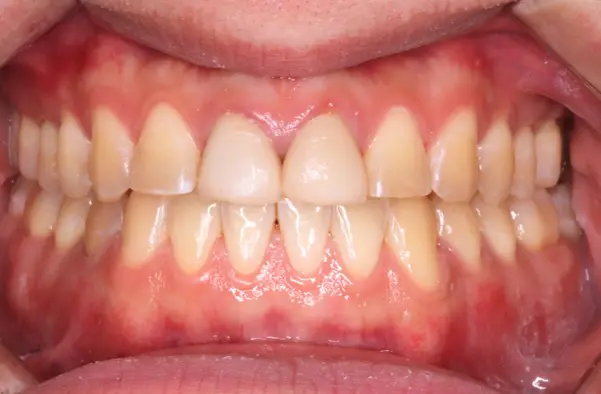

Before

After